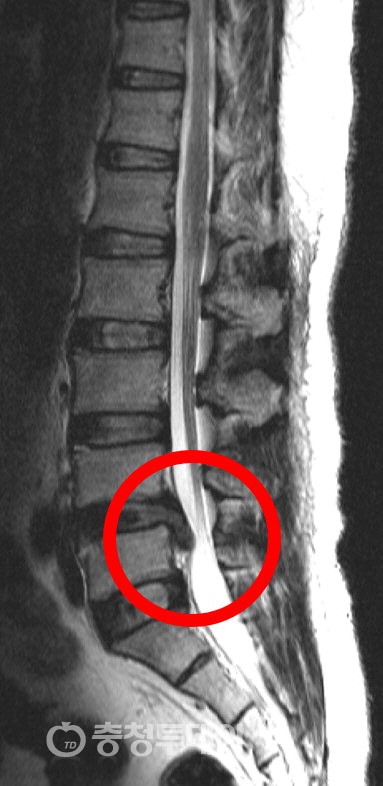

척추 이상

추간판 탈출증, 척추 협착증 또는 척추 측만증과 같은 척추 내의 구조적 이상은 허리 통증을 유발할 수 있습니다. 추간판 탈출증은 척추 디스크의 부드러운 내부 코어가 바깥쪽으로 돌출되어 주변 신경에 영향을 미치고 국부적이거나 방사성 통증을 유발할 때 발생합니다. 척추관이 좁아지는 것을 특징으로 하는 척추관 협착증은 신경 뿌리를 압박하여 통증, 무감각 또는 쇠약을 초래할 수 있습니다. 척추의 비정상적인 만곡인 척추측만증은 근육 불균형과 불편함을 초래할 수 있습니다.